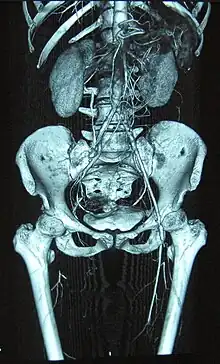

Complete occlusion of the right and stenosis of the left femoral artery as seen in a case of thromboangiitis obliterans